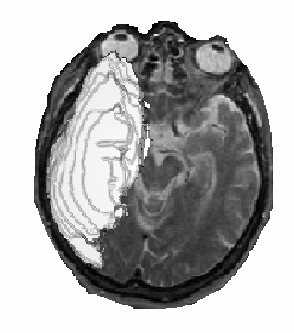

A second example of the use of neuroatlas, which shows an brain haemorrhage in a 3D axial serial section image

Figure 3. 3D image of a large haemorrage. This type of image can be used e.g. in planning

of neurosurgery.